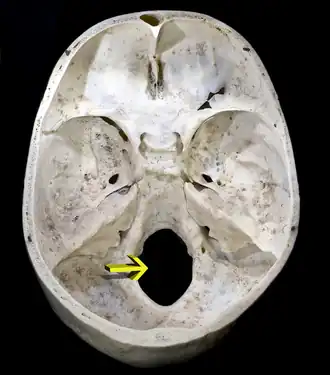

![]() Upper surface of the base of skull; the hole indicated by an arrow is the foramen magnum. | |

The foramen magnum (Latin for 'great hole') is a large, oval-shaped opening in the occipital bone of the skull. It is one of the several oval or circular openings (foramina) in the base of the skull. The spinal cord, an extension of the medulla oblongata, passes through the foramen magnum as it exits the cranial cavity. Apart from the transmission of the medulla oblongata and its membranes, the foramen magnum transmits the vertebral arteries, the anterior and posterior spinal arteries, the tectorial membranes and alar ligaments. It also transmits the accessory nerve into the skull.

The foramen magnum is a large, oval-shaped opening (foramen) in the occipital bone of the skull.[2] It is present in humans, and in many other animals. Anteriorly, it is bounded by the basiocciput.[2] Posteriorly, it is bounded by the supraocciput.[2] Laterally, it is bounded by the occipital condyles.[2]

On the occipital bone, the foramen magnum presents two midline cephalometric landmarks. The opisthion is the midpoint on the posterior margin of the foramen magnum. The basion is located at the midpoint on the anterior margin of the foramen magnum.

The alar ligament, which is attached on each side to the tubercle of occipital condyle, divides the foramen magnum into an anterior smaller compartment and a posterior larger compartment.[3]